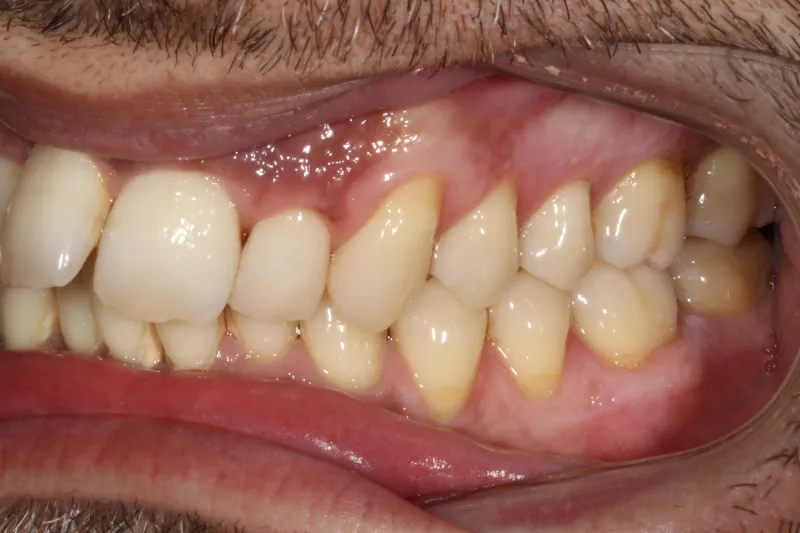

Upper Arch Invisalign to fix overcrowded teeth